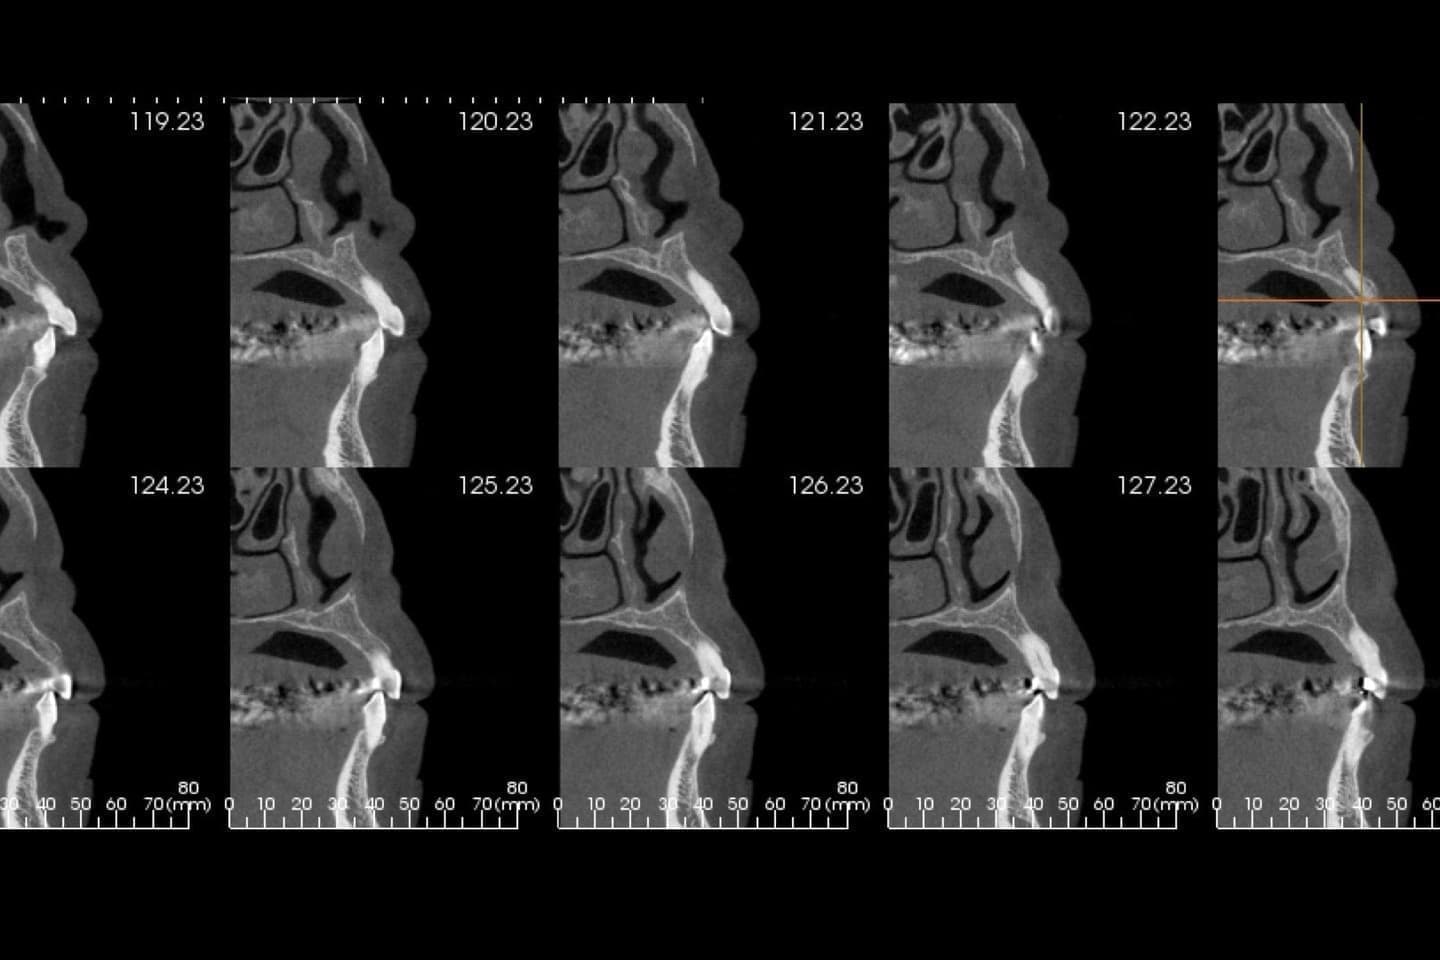

歯周病学会歯周病専門医による正確で緻密な治療

歯周病専門医は、歯周病治療において予知性の高い、 包括的歯科診療を患者様に提供するスペシャリストです。

歯周病専門医、指導医が診断、治療を行う歯科医院です